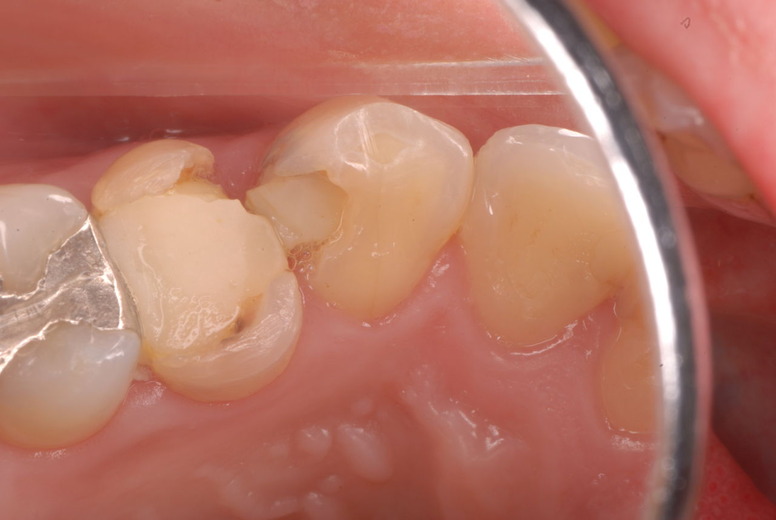

ご自分でやられても歯茎から血が出ないと話をされていましたが、私がブラシを当てると悲惨な状態であることがわかりました。

何故歯が悪くなるのか、歯周病で抜けるのか分からなければ何を入れても歯は悪くなり抜けていくのです。

病気を治しましょう。それから差し歯や入れ歯を入れましょう!物を入れれば入れるほど、磨き方や掃除の仕方が上手にならなければ、すぐ抜けてくるのです。